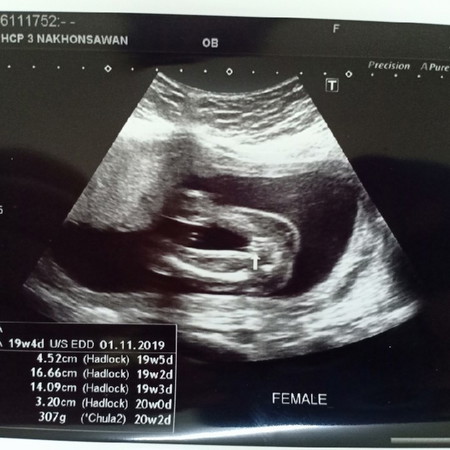

คุนแม่บ้านไหนทราบบ้างค่ะ 19week5dแต่น้ำหนักลูก320gน้ำหนักน้อยไปไหมค่ะ

บ้านนี้19วีคเหมือนกันค่ะ น้ำหนักแค่289gเอง น้อยมากกังวลมากด้วยค่ะ